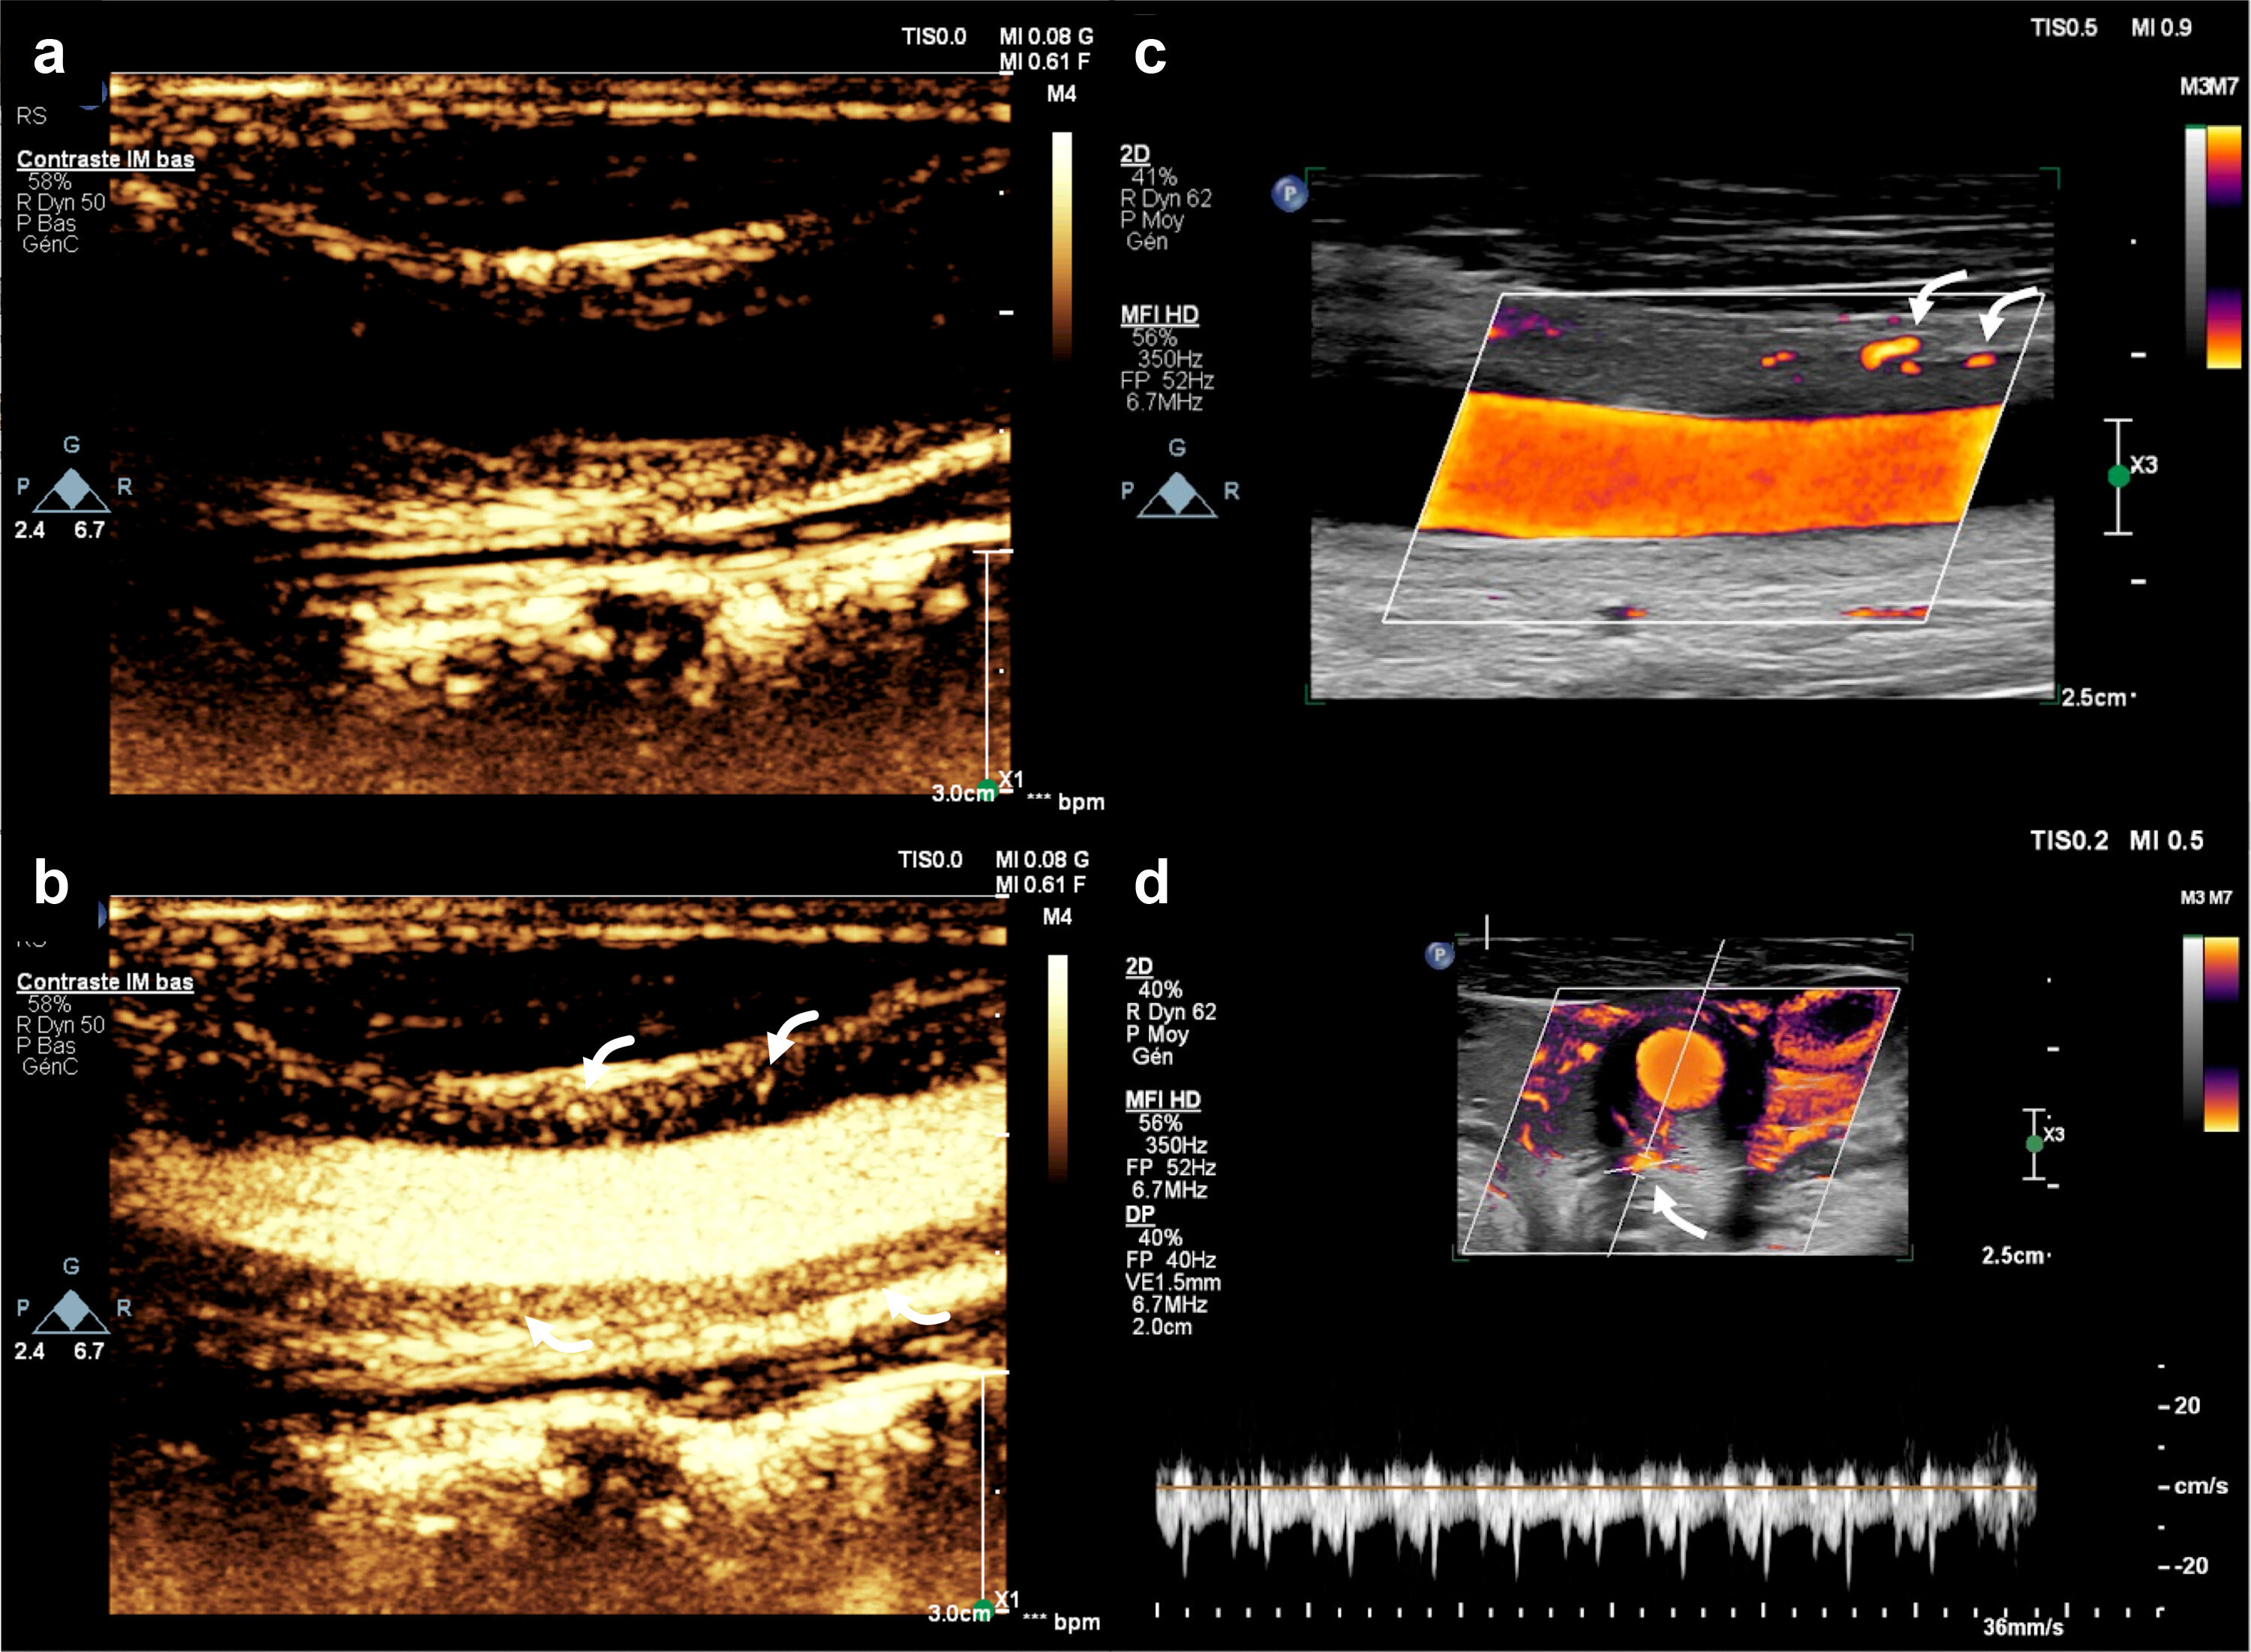

ICONOGRAPHIE personnelle et autres : FUJIFILM Puissance /eFLOW MC / DFI MC

1/ Les malformation veineuses

2/ Une interface plaque /carotide de meilleure qualité

3/ La vicariance en cas de collatérales de petits calibres

4/ Recherche de flux intra plaque mais avec difficulté ; problème de sonde je pense

5/ Les anfractuosités de la plaque carotidienne

5/ En de dissection artérielle

6/ Tumeur glomique de la bifurcation carotidienne

9/ Toutes atteintes artérielle périphérique de type inflammatoire